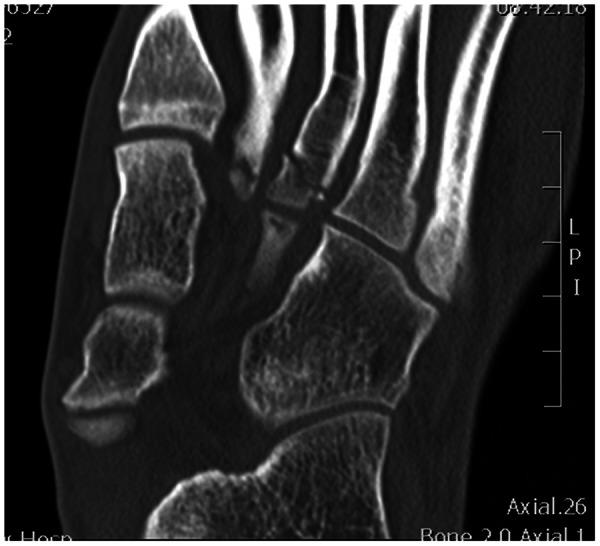

An 18-year-old military cadet reported to a direct-access sports physical therapy clinic with foot pain. Despite negative radiographic findings, there was a high suspicion for Lisfranc injury based on the injury mechanism and physical examination. A computed tomography scan demonstrated an oblique fracture through the base of the third metatarsal, a small marginal fracture at the plantar base of the second metatarsal, and a subtle diastasis. Two days following his injury, he underwent an open reduction and internal fixation, completed subsequent rehabilitation, and returned to full activity approximately 1 year following injury.

一名 18 岁的军校学员因足部疼痛到直接就诊的运动物理治疗诊所就诊。尽管影像学检查未见异常,但根据损伤机制和体格检查,高度怀疑存在跖跗关节损伤。计算机断层扫描显示第三跖骨基底部斜形骨折,第二跖骨足底基底部有小的边缘骨折,以及轻微的分离。损伤后两天,他接受了切开复位内固定术,完成了随后的康复治疗,大约在受伤后 1 年恢复了完全活动。